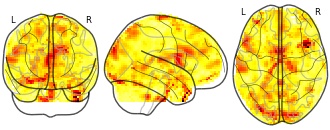

"description": "Multi-modal analysis in BPD. Brain regions exhibiting greater gray matter and enhanced activation during emotion processing in BPD compared to healthy controls. Note: Results were thresholded at p<.0025. Note2: Results were updated (see Erratum for this publication).",